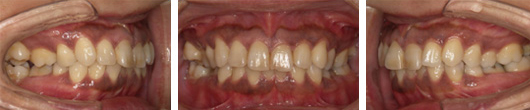

治療前-治療後

初診時の口腔内写真では左の咬合平面が下がっていました。

治療後はきれいに整っています。

左上下顎臼歯部に著しい叢生があり、下顎臼歯部が大きく舌側へ傾斜していました。左はもちろん、右側も歯並びが崩れていて、右ではほとんど咬んでいなかったそうです。